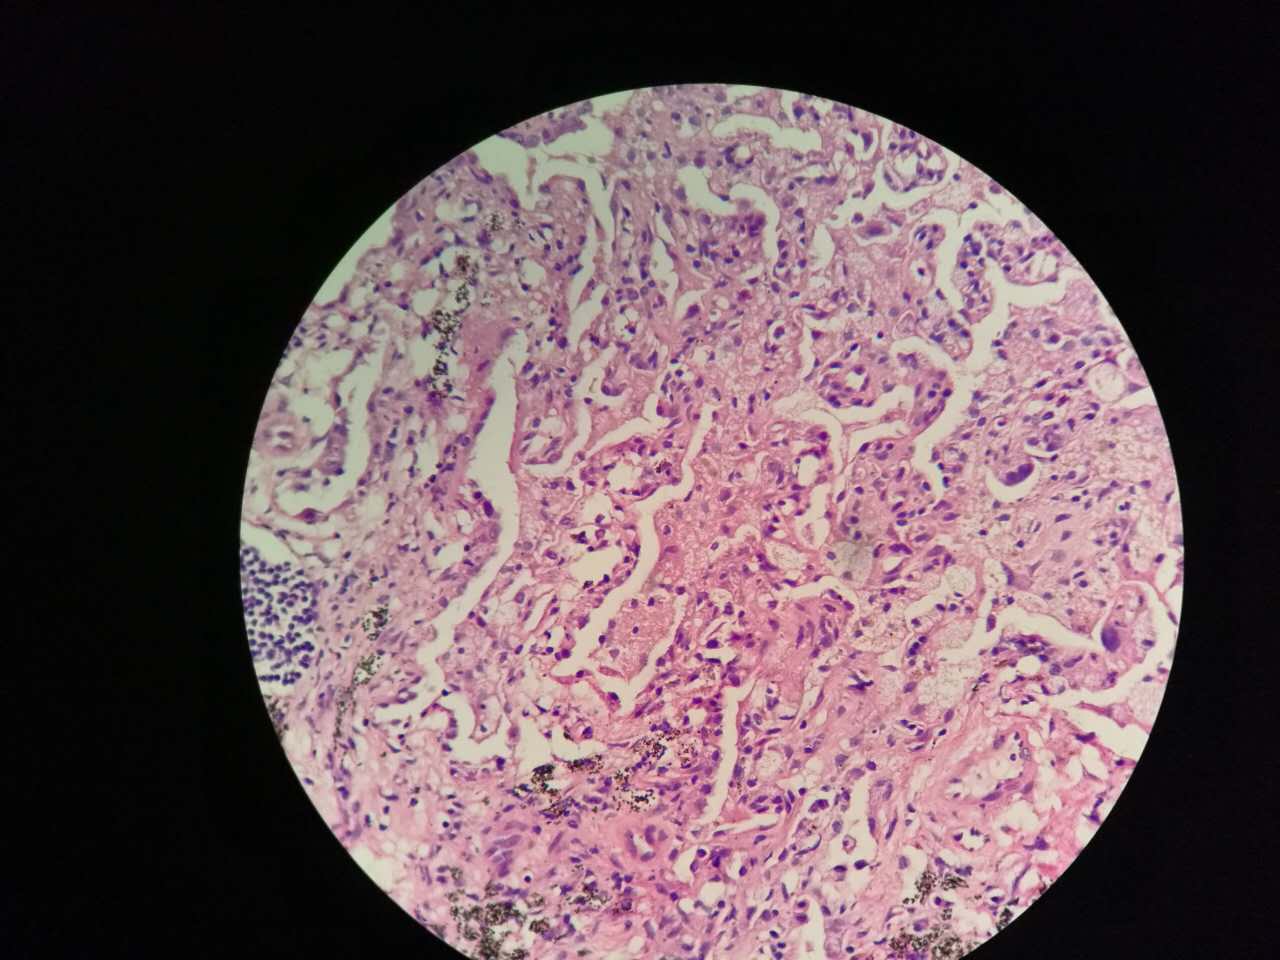

粘液型腺癌

粘液型腺癌是原发肺腺癌中的一种特殊类型

细胞内外含较多粘液

粘液型腺癌,细胞内粘液多,有点儿像支气管的粘液腺

单纯的粘液腺,没有浆液腺

细胞外粘液湖

粘液腺癌起源于细支气管和肺泡

这一幅的上方都是黏液湖

下方是正常肺泡

细胞内白颜色区是粘液,细胞外洋流样的也是粘液(湖)

黏液湖里可以飘着一些细胞,吞噬细胞及肿瘤细胞。

肿瘤细胞飘出去可以种植于肺泡上。

粘液型腺癌的肿瘤细胞排列整齐,核位于基底,细胞呈柱状。

肺泡间隔(间质)经常比较细